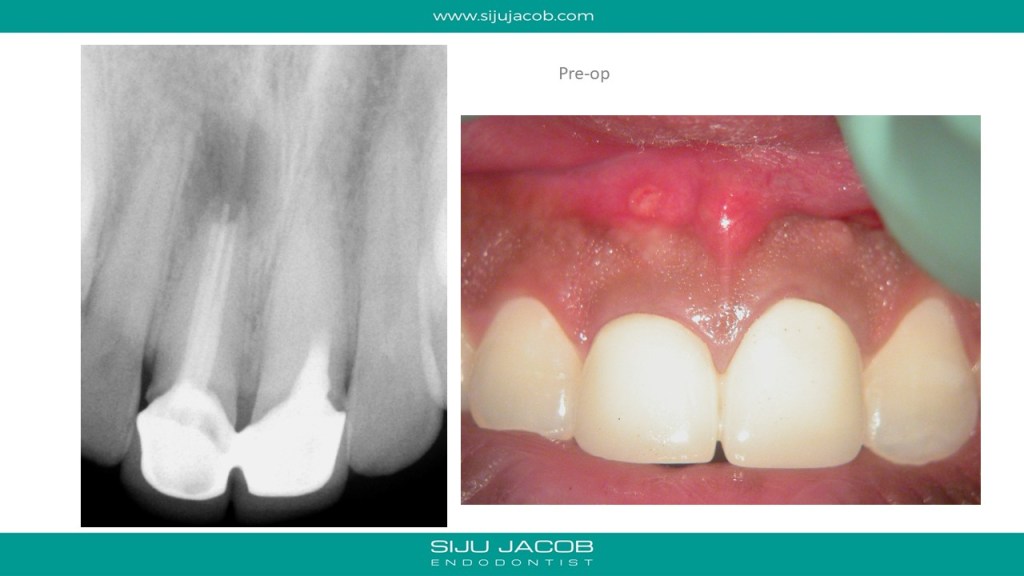

This was a patient who traveled from abroad from Treatment. We had only 9 days to do his treatment. So, we did endo and immediate surgery.